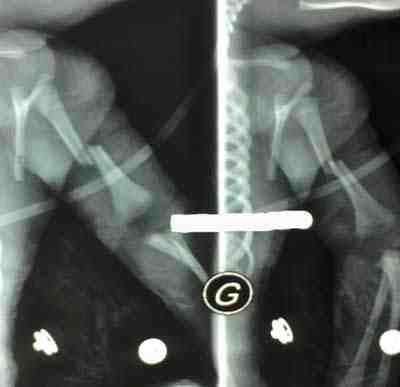

- Radiografía de miembro superior izquierdo: Presenta lesión de pérdida de continuidad ósea con desplazamiento (Fractura Húmero Izquierdo desplazada).

Radiografías:

Figura 2. Radiografía Simple del miembro superior izquierdo (Fractura de Húmero Izquierdo desplazada)

Figura 3. Evolución Radiológica de la fractura: